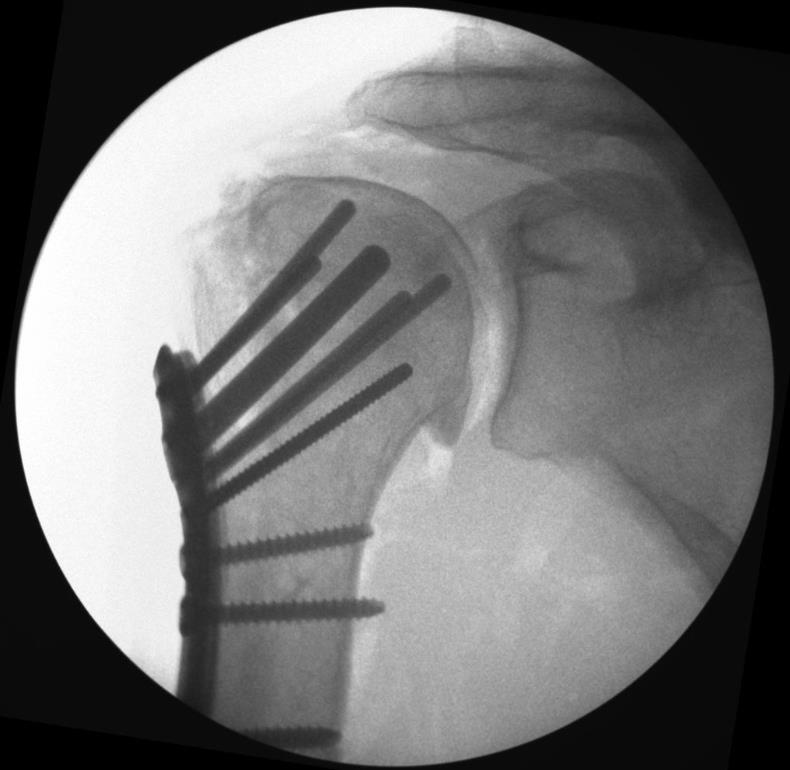

Proximal Humerus Fixation System

• The Proximal Humerus Fixation System (PHFS) from Skeletal Dynamics is a plate-and-peg/screw construct designed around proximal humeral anatomy for fixation of fractures, fracture-dislocations, osteotomies, and non-unions of the proximal humerus.

• The system centers on a proximal humerus plate with smooth locking pegs, locking/compression screws, and a central fixed-angle peg, with both straight and curved plate options.

• the PHFS has multiple, divergent, fixed-angle pegs oriented toward the humeral head dome to achieve broad subchondral spread and support the articular surface, with the goal of resisting varus collapse.

• Fluoroscopy in AP and lateral views is used to verify that the wire is center–center and follows the desired 135 degree trajectory.

• An appropriately sized 6.0 mm smooth locking central peg is inserted and locked into the plate with the T-10 driver to provide a strong central column.

• Final fluoroscopy confirms reduction, peg and screw lengths, plate height relative to the greater tuberosity, and absence of joint penetration or subacromial impingement risk.